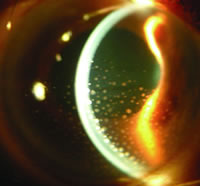

2.螢光素眼底血管造影檢查 對診斷有很大幫助。Behcet病性葡萄膜炎典型地表現為視網膜血管炎,螢光素眼底血管造影檢查對評價視網膜血管改變有重要價值。它可發現臨床上無任何視網膜、視網膜血管改變的視網膜血管炎 可以動態評價視網膜炎和視網膜血管炎的變化和藥物治療作用,可以監測炎症對視網膜血管和視盤血管損害的範圍及其程度。

Behcet病性葡萄膜炎的螢光素眼底血管造影檢查可發現以下多種改變(圖1):

(1)瀰漫性的視網膜毛細血管滲漏、視盤血管滲漏和受累大血管的滲漏。

(2)後期視網膜血管壁染色。

(3)視網膜毛細血管閉塞、無灌注區 側支循環形成和視網膜新生血管。

(4)黃斑囊樣水腫、黃斑裂孔、視網膜前膜。

除視網膜改變外,螢光素虹膜血管造影還可發現虹膜血管有螢光素滲漏,提示血-房水屏障功能遭到破壞。